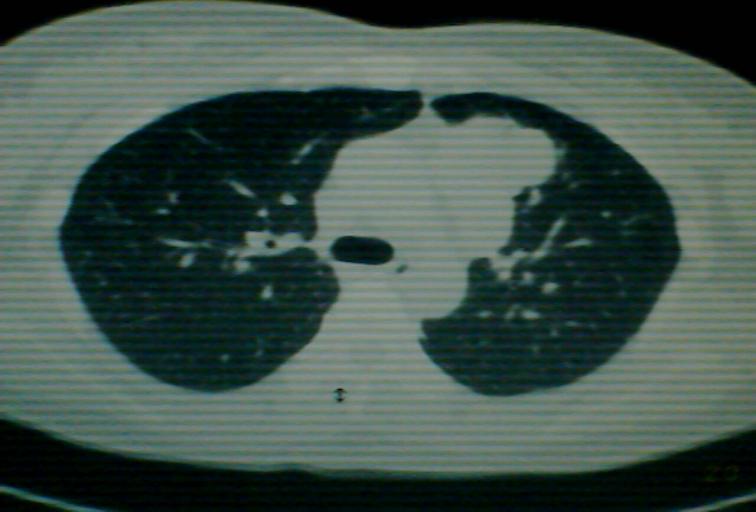

以下是引用狙击手在2007-4-10 22:46:00的发言:[br]考虑:左上纵膈旁型肺癌。理由:1,肿块与纵隔间有分隔;2,肿块呈分叶状;3,肿块突出面圆心在肺内;4,纵隔左移;5,纵隔内器官未见受压征象。